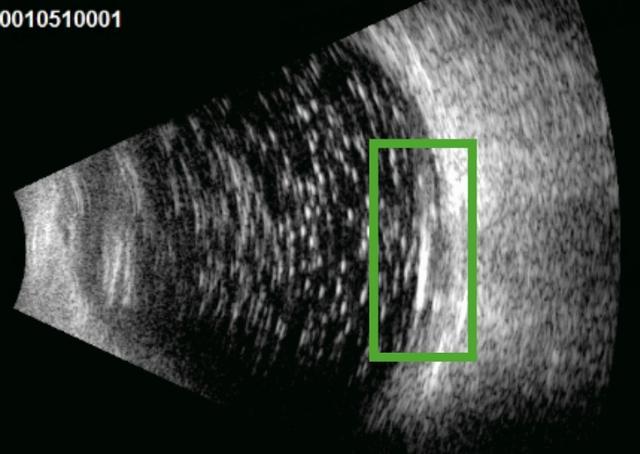

▲绿框所示右眼玻璃体腔可见弧形强回声,其后伴“彗尾征”